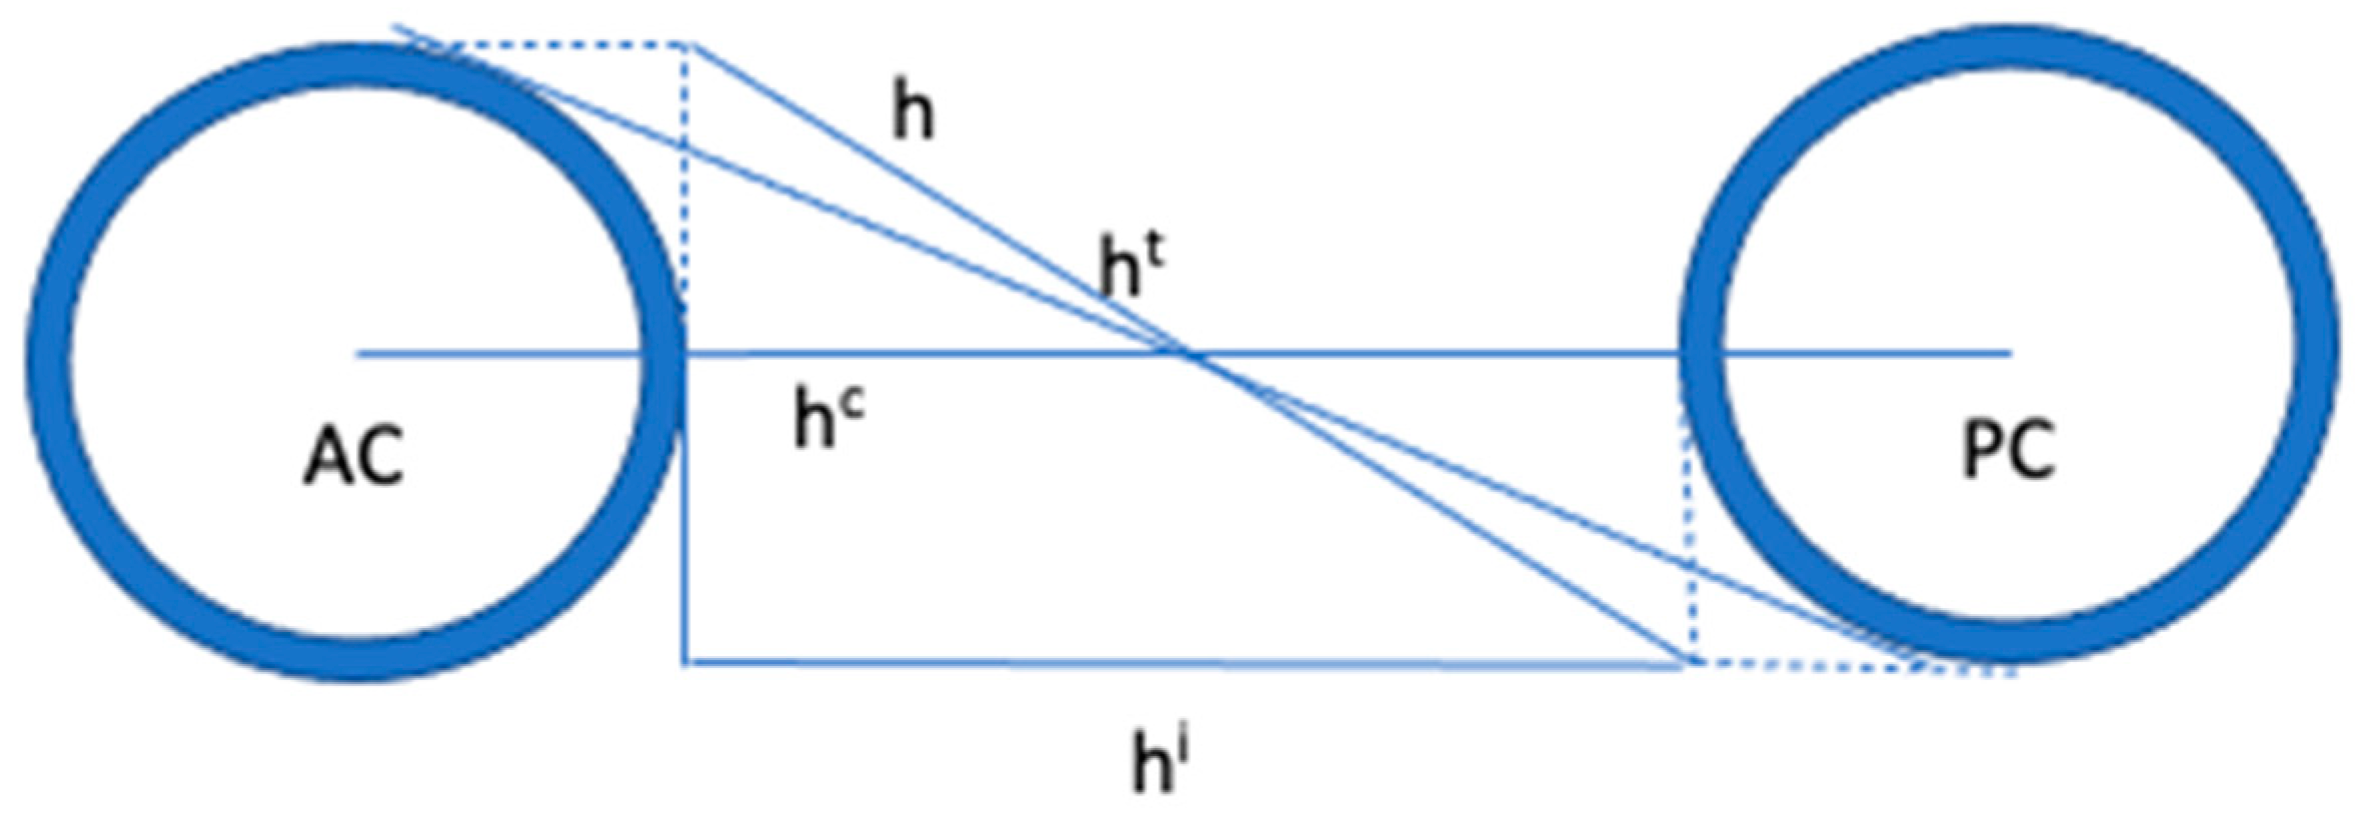

4. The Proportional System of Talairach